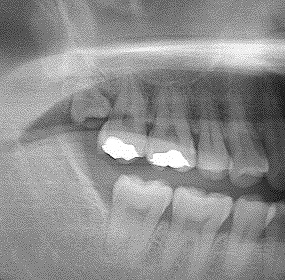

右上の完全埋伏歯の難抜歯 30代男性 いつも歯茎が腫れる|お知らせ |広島市安佐南区の歯科医院 右上の完全埋伏歯の難抜歯 30代男性 いつも歯茎が腫れる トップ お知らせ・ブログ お知らせ 右上の完全埋伏歯の難抜歯 30代男性 いつも歯茎が腫れる 右上の完全埋伏歯の難抜歯 30代男性 いつも歯茎が腫れる ここに親知らずが埋まっています 親不知のせいで歯茎が腫れています デンタルレントゲンにて親知らずが少し見えます パノラマにて様相がよくわかります 切開にて頭が見えてきています 抜歯していきました 縫合して終了となります 抜歯した歯になります これが原因で腫れていました Web診療予約 初めての方へ 選ばれ続ける理由 院内設備について 歯が痛いしみる一般歯科 歯がぐらぐらする歯周病 健康な歯を保ちたい予防歯科 子供の虫歯予防をしたい小児歯科 銀歯をセラミックに審美歯科 白い歯を目指しませんか?ホワイトニング 矯正専門医がいるので安心矯正歯科 抜けた歯を補いたいインプラント・入れ歯 医院案内 スタッフ紹介 メリィハウス歯科クリニックオフィシャルホームページ ラベンダー歯科クリニックオフィシャルホームページ お知らせ・ブログ ホーム 診療科目 一般歯科 歯周病治療 予防治療 小児歯科 審美治療 ホワイトニング 矯正歯科 入れ歯・インプラント マウスピース矯正 初めての方へ 院長・スタッフ 設備紹介 医院案内・アクセス メニューを閉じる